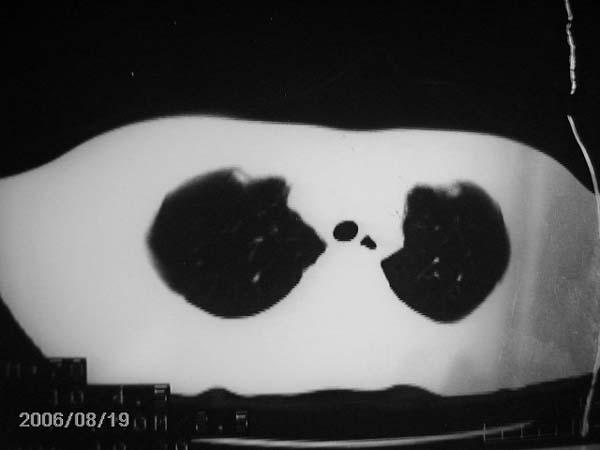

男,13岁,发烧半月,干咳无痰,正规使用抗生素半月,现在仍是午后低烧!!!未做痰检

图片太黑 大叶性肺炎

图片照得太黑了,看不太清楚。

图片还是看不太清,应尽快ppd试验及痰检,如无异常,可纤维支气管镜检排除异物可能。

前段病变以炎症为多,应继续抗炎治疗,一般炎性病灶需1个月后才遂渐完全吸收。